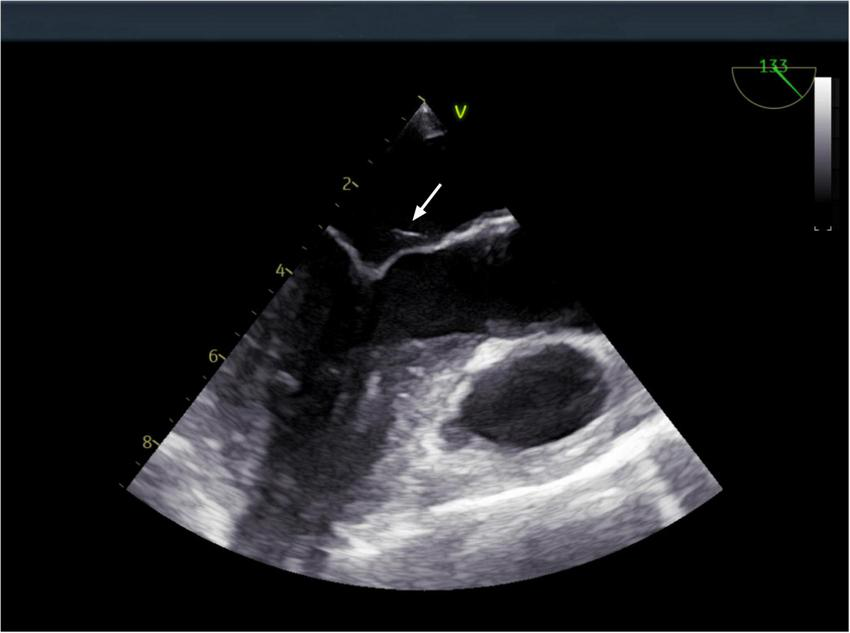

However, after completing 1 year of anti-tuberculosis therapy, the patient was re-admitted on March 15, 2024, due to recurrent low-grade fever. Repeat abdominal CT (Figure 1) showed progression of the hepatic lesion (now 5.1 × 2.0 × 3.6 cm) and persistent peritoneal thickening. Transesophageal echocardiography (TEE) revealed vegetations on the mitral valve (Figure 4), compatible with infective endocarditis.

FIGURE 4

Transesophageal echocardiography: a vegetation on the mitral valve was detected. The arrow indicates the location of the mitral valve vegetation.

A repeat ultrasound-guided biopsy of the abdominal lesion was performed on March 20, 2024. Histology again showed granulomatous inflammation with focal necrosis (Figure 3), and acid-fast staining remained negative. Crucially, metagenomic next-generation sequencing (mNGS) analysis of the biopsy tissue detected Coxiella burnetii-specific sequences, with 66 unique reads and a relative abundance of 66.01%. Based on these findings, the patient’s dialysis history, and immunocompromised status, a definitive diagnosis of chronic Q fever with infective endocarditis was established. Anti-tuberculosis medications were immediately discontinued, and targeted therapy with doxycycline (0.1 g twice daily) was initiated. The patient was discharged on March 27, 2024, on doxycycline monotherapy.

During the patients second hospitalization, TEE demonstrated a mitral valve vegetation. In combination with metagenomic next-generation sequencing (mNGS) results, the diagnosis was suspected to be Q fever endocarditis. Q fever endocarditis is often associated with pre-existing valvular heart disease, immunosuppression, or pregnancy (22–24). Currently, doxycycline is the first-line treatment for Q fever (6),but in cases complicated by infective endocarditis, adjunctive hydroxychloroquine is recommended (25). Given this patient’s hypertensive retinopathy, doxycycline monotherapy was chosen, and the patient has been monitored for 14 months without recurrence.